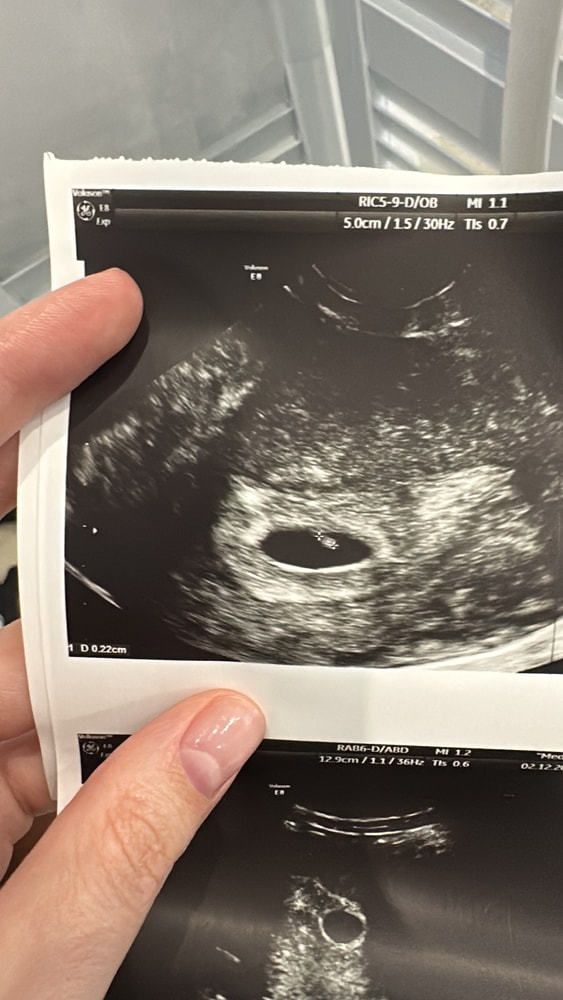

Узи 6 недель 1 день

УЗИ, КТГ, доплерВсем привет! Сегодня была на узи, с призрачной надеждой увидеть пульсацию сердечка ♥️

ПЯ 13 мм, КТР 2 мм, сердцебиение+ 🤗

Сказали прийти через 2 недели еще раз.

Немного отстаем по сроку, овуляция была не на 14, а на 17-18дц) так что не критично🤞